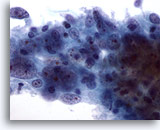

Figure 6

Breast FNA, Fibroadenoma.

Typically, fibroadenoma aspirates contain large branching sheets of benign ductal cells as seen in this illustration. 20x

Figure 6

Breast FNA, Fibroadenoma.

Typically, fibroadenoma aspirates contain large branching sheets of benign ductal cells as seen in this illustration.

20x